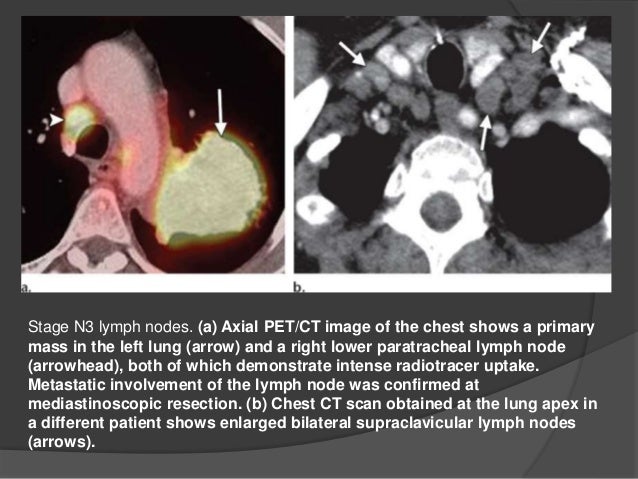

Non Small Cell Lung Cancer Staging Stages Of Lung Cancer